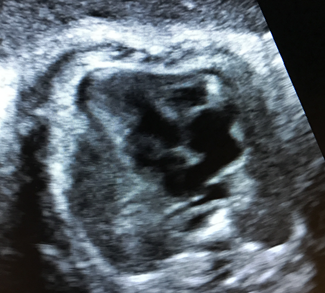

We present the case of a pregnant woman with a 35-week fetus referred for suspicion of fetal heart malformation. The fetal echocardiogram showed severe hypoplasia of the left ventricle (Figure 1). A very small donut-shaped left ventricle with severe mitral valve stenosis is observed. The patient was managed by being referred to a tertiary center where the diagnosis of LVHS was confirmed and he remained under control at said center until birth. A 39-week-old newborn was born at the tertiary level, small for gestational age, and the diagnosis of LVHS, mitral-aortic hypoplasia, accentuated aortic arch hypoplasia was confirmed. His parents decided not to operate on their son and to have compassionate management due to the severity of the cardiac malformation.

Figure 1 The image shows a left ventricle with severe hypoplasia and the mitral valve with severe, almost atretic stenosis.